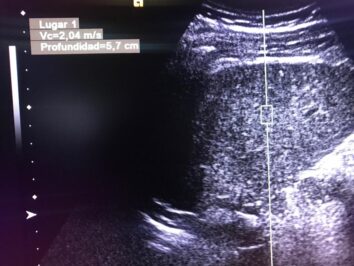

Masculino de 52 años, con cirrosis hepática. La elastografía ecográfica evidencia fibrosis Categoría F3 según escala de METAVIR y la presencia de múltiples nodulaciones, que en su mayoría son menores a 2 cm.

En este contexto, toda nodulación mayor de 1 cm, debe ser evaluada idealmente con RM trifásica con secuencia de Difusión , para discriminar si se trata de nódulos de regeneración , nódulos displásicos o hepatocarcinoma.